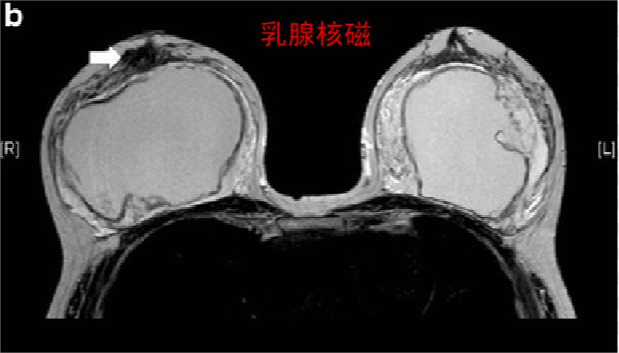

乳房植入物女性的评估;

7植入物患者的乳房 MRI

乳腺MRI 是检测乳房植入物破裂的最敏感技术,植入物的存在不会影响 MRI 对乳腺癌检测的敏感性 。

注意:在没有症状的情况下,不需要通过乳房 MRI 筛查乳房植入物的完整性。